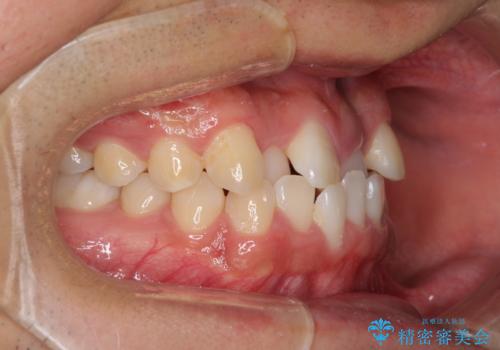

美容歯科でも断られた 著しい前歯のクロスバイトをワイヤー矯正で改善

- 前歯のクロスバイトを気にして来院された患者様です。

美容専門の歯科医院を受診したところ、セラミックでの改善は無理と断られてしまったとのことでした。

歯がすり減って不揃いの形態となっていますが、まずは矯正治療によりクロスバイトを改善することとしました。